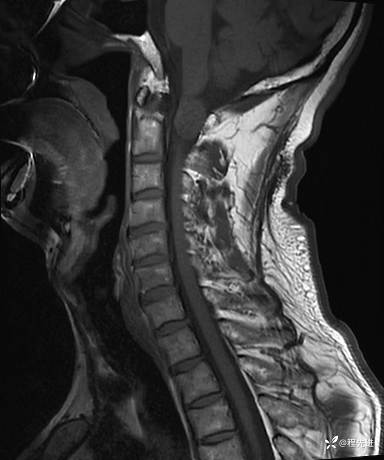

MRI平扫+增强:

T1增强: